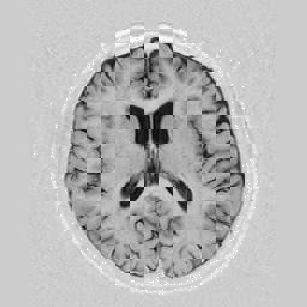

Lastly, Figure [*] shows 10 iterations at level 2, 6 iterations at level 1, and 6 at level 0.

Figure: Multi-scale NRR. From left to right, top then bottom: before NRR; after 10 iterations of NRR at level 2; after another 6 iterations of NRR at level 1; after 6 more iterations at level 0.